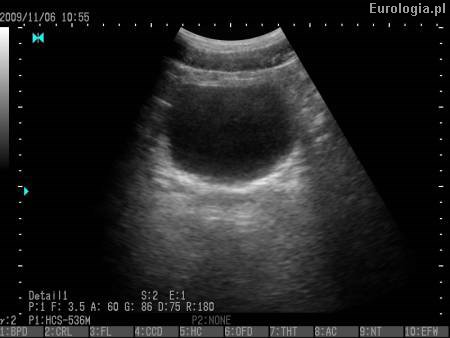

Video: Obraz USG układu moczowego.